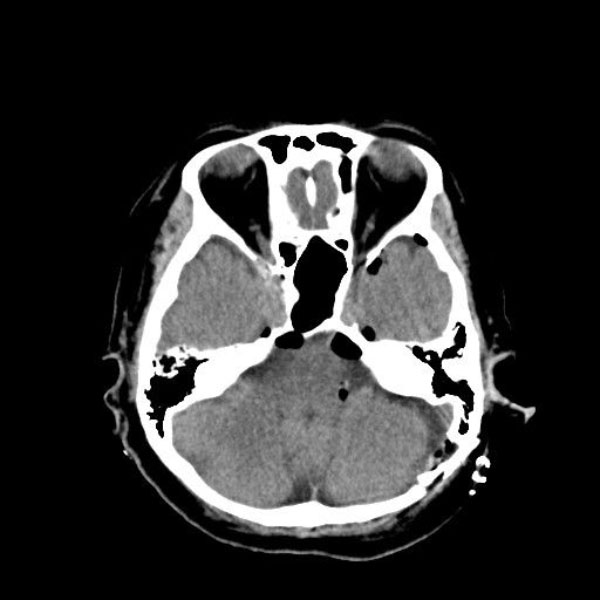

症例 '25年10月

No.

559

当院外来

'25年10月

50代

左顔面痙攣

(痙攣をとること)

手術前

減圧前

減圧後

術後血管撮影